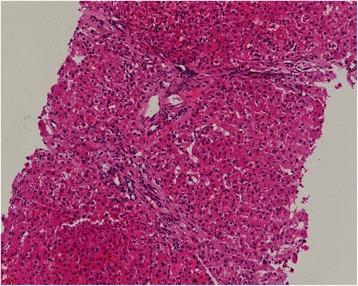

Portal hypertension as the initial manifestation of POEMS syndrome: a case report.

We report a 46-year-old Chinese male, a teacher, presenting with portal hypertension. Electromyography revealed peripheral neuropathy. Immunofixation showed monoclonal immunoglobulin A lambda protein. The diagnosis of POEMS syndrome was established. After treatment of lenalidomide combined with dexamethasone over 2 years, the patient achieved a considerable improvement.

https://cdn.ncbi.nlm.nih.gov/pmc/blobs/c902/5425989/b82ef80745fe/12878_2017_78_Fig2_HTML.jpg

https://cdn.ncbi.nlm.nih.gov/pmc/blobs/c902/5425989/bf52c6aae534/12878_2017_78_Fig1_HTML.jpg